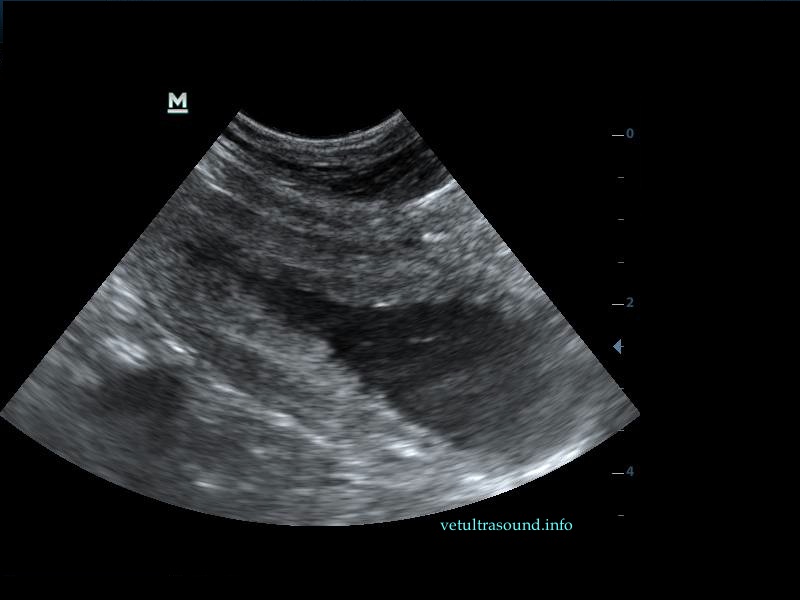

Η πάχυνση του τοιχώματος και η δοκίδωση του βλεννογόνου είναι εμφανής σε όλες τις εικόνες. Πολλές φορές οι λαγόνιοι λεμφαδένες μπορεί να είναι ήπια διογκωμένοι και να έχουν αντιδραστική ηχομορφολογία. Ο έλεγχος με έγχρωμο Doppler του τοιχώματος της άδειας κύστης μπορεί να μας δείξει ροή αίματος στα αγγεία της κύστης. Αντίθετα, είναι πιθανό, όσο η κύστη γεμίζει με ούρο η ροή αίματος να μην είναι ορατή με το Doppler. Αυτό συμβαίνει συχνά στη χρόνια βακτηριακή κυστίτιδα λόγω της ίνωσης του τοιχώματος της ουροδόχου και αυτή είναι μία από τις αιτίες της μη ανταπόκρισης στη θεραπεία. Η συγκεκριμένη παθοφυσιολογία έχει μελετηθεί στον άνθρωπο με την βοήθεια ενδοσκοπικού υπερήχου.

The increase of thickness of the urinary bladder wall and the striation of the mucosa is evident. Inguinal lymphnodes are usually prominent and mildly enlarged. Colour Doppler may reveal the blood flow of the mucosa of the empty urinary bladder, whereas the blood flow in a full bladder appears decreased. This could be because of the fibrosis of the urinary bladder wall and could explain why sometimes chronic conditions like these do not respond well to antibiotics. This pathophysiology has been studied in humans with the use of endoscopic ultrasound.